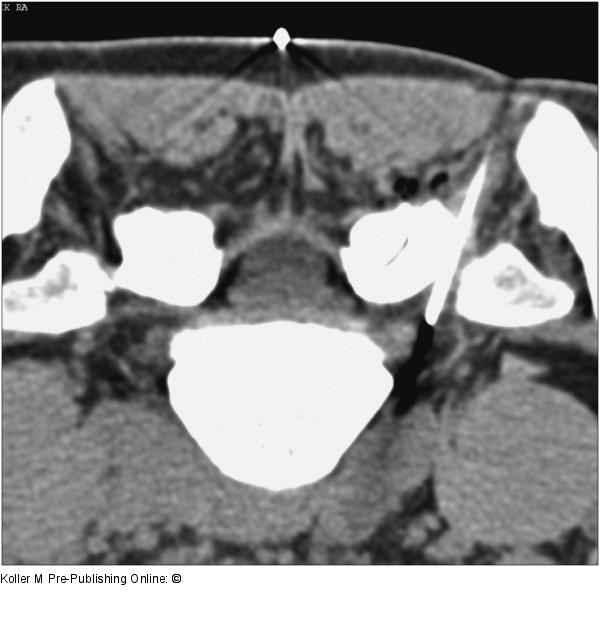

Abbildung 8: Nervenwurzelinfiltration CT-gezielte Nervenwurzelinfiltration |

Abbildung 8: Nervenwurzelinfiltration

CT-gezielte Nervenwurzelinfiltration |